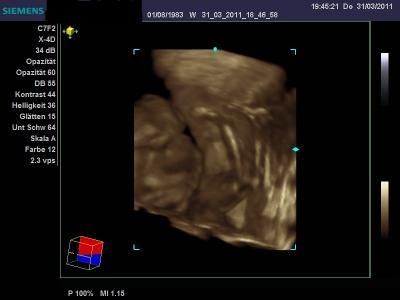

Habe jetzt fast 50 Bilder insg. von unserem kleinen Luis :-) Der Arzt war super wobei er meinte das wir nicht wirklch Glück hatten weil immer was vor dem Gesicht war und weil es ja erst die 21 Woche ist ... ist noch recht Früh wir werden das selbe in 4 bis 5 Wochen nochmal machen. Habe 14 Bilder so und den rest auf dem USB stick mit bewegeung manche sogar . Aber andere hatten da ja schon viel mehr Glück mit den Bildern :-( Also das sie deutlich sind usw... er hatte immer was vor dem Gesicht und so konnte der Arzt es nicht scharf stellen. Es war auch Wahnsinn wie er sich bewegt hat wie wild....

Bild zu War beim 3 d und 4 d Ultraschall  2 Stundenlang - Forum für August - Mamis